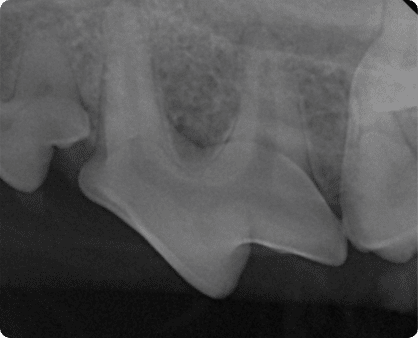

육안으로는 확인이 어려운 잇몸 아래, 치아 뿌리 및 턱뼈의 병변을

치과 방사선으로 진단

치수 감염 또는 심한 치주염으로 인해

치아 뿌리 끝에 고름주머니가 생기는 질환.

심해질 경우, 눈 밑 병변이나 턱뼈의 골절 유발 가능